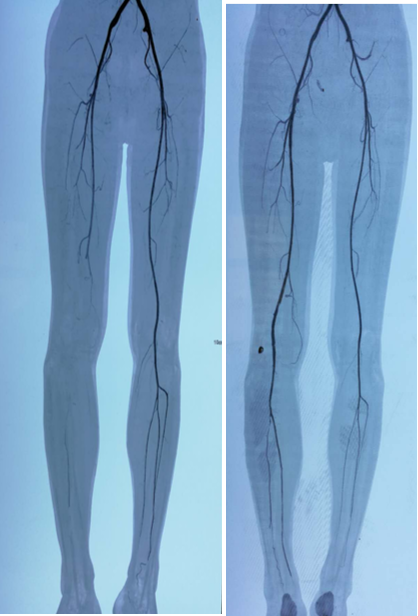

图:术前、术后CT

图:术前CT